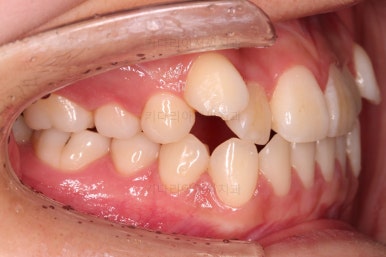

오늘 연산동교정치과 키다리아저씨치과에서 소개해 드릴 환자분은 덧니때문에 교정하고자 하셨던 분입니다.

나이 : 19세

총 치료기간 : 1년 1개월(총 13개월)

사용한 장치 : 자가결찰 세라믹(엠파워 클리어, Empower clear) + 미니스크류

입 안을 보면 밑에 치열이나 다른 부분은 비교적 양호한데 유달리 윗니 송곳니만 위치가 좋지 못하네요.

비발치

이번 환자분은 보기에는 송곳니가 덧니라 많이 삐뚤어 있는 것 같지만 치료는 비발치, 즉 발치 없이 진행했는데요.